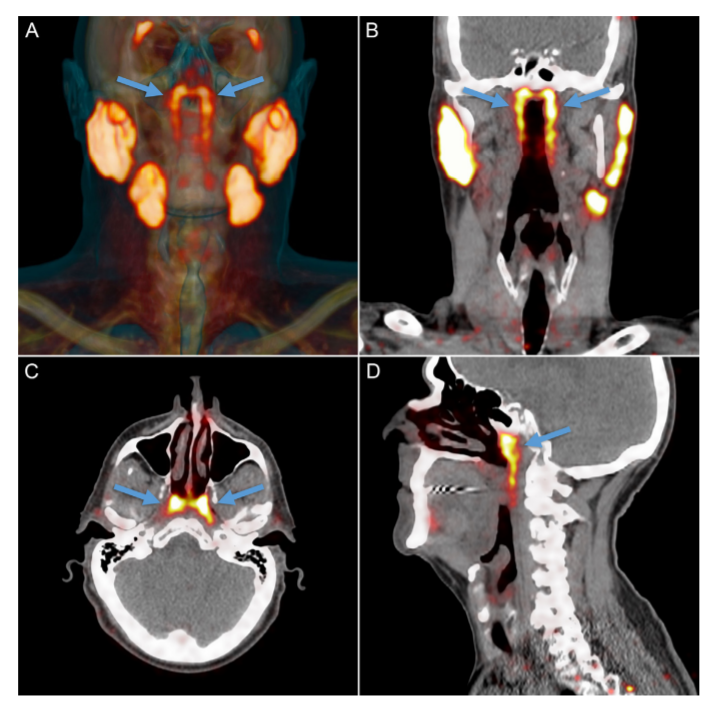

而这次新发现的隆凸唾液腺位于鼻子后面一块被称为咽鼓管隆凸的软骨上 , 平均长度约1.5英寸(即3.9厘米) 。

Vogel是在探查头部、颈部或脑部癌症放疗后的唾液腺损伤(导致消化、语言和口腔感染增加等问题)时 , 发现这组从未被描述和记录过的颈部唾液腺的 。

为了证实人体的隆凸唾液腺这一最新发现的非偶然性 。 Vogel及其同事对100名患者进行了扫描(由于研究者是聚焦前列腺癌 , 所以其中99位患者为男性) , 还解剖了两具尸体 , 最终发现所有人都拥有这一“新的”腺体 。